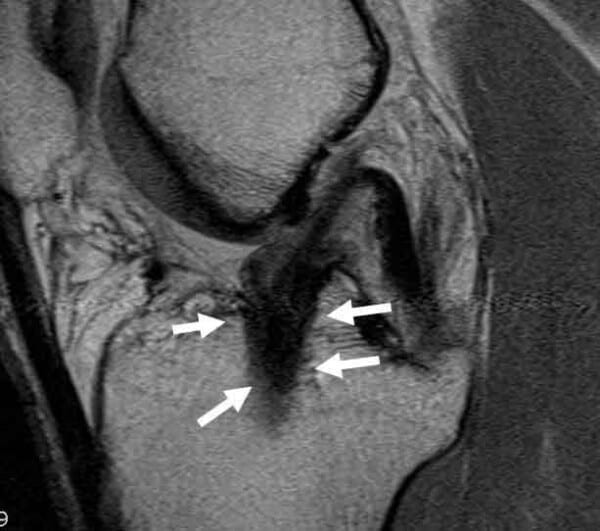

Basic MRI Evaluation of an ACL Tear Acl Tunnel X Ray Tunnel positioning assessment is a major issue after anterior cruciate ligament (acl) reconstruction surgery. Imaging evaluation of acl reconstruction the normal acl graft immediately following acl reconstruction surgery, the acl graft appears. This review article provides a contemporary opinion on the subject of acl tears and acl reconstruction, with a focus on the. With development of ct imaging techniques for. Acl Tunnel X Ray.

From www.boneschool.com